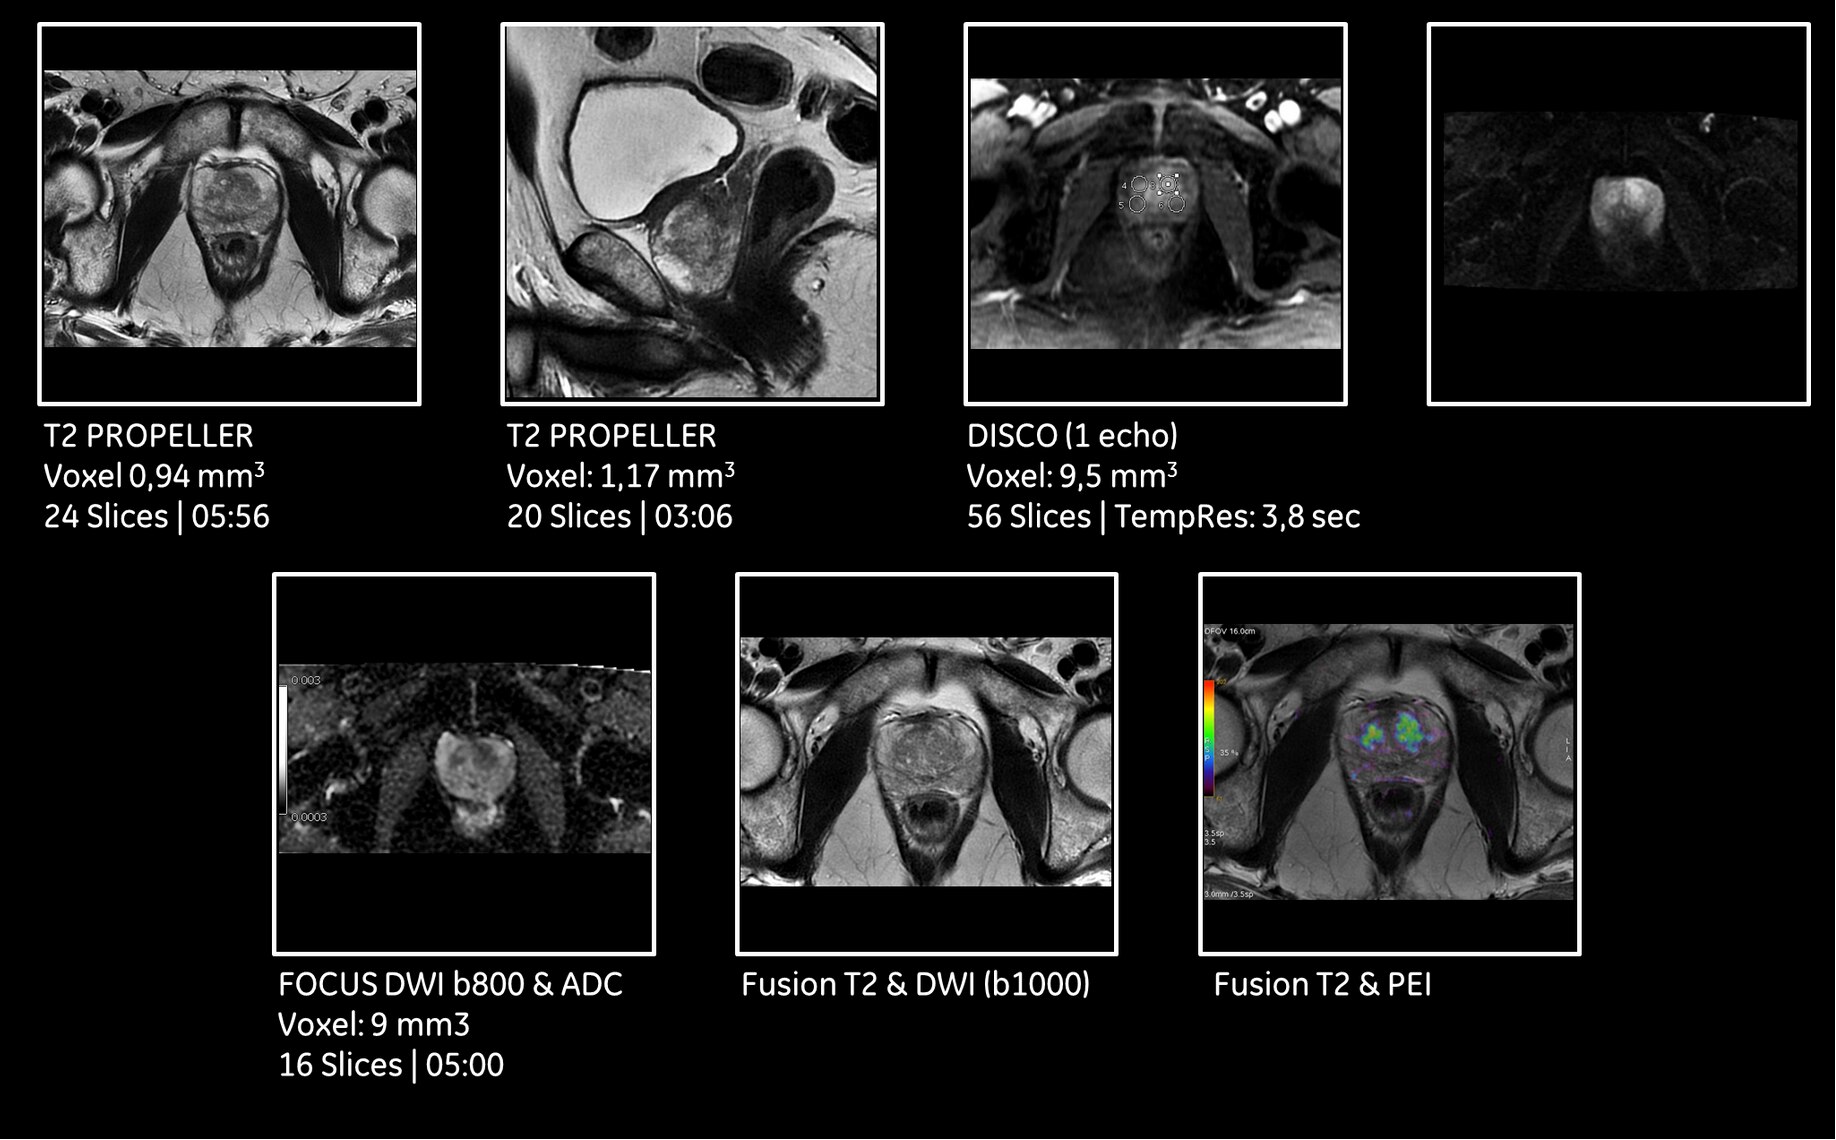

With its free-breathing imaging applications and advanced motion correction software, SIGNA™ Pioneer will compensate for patient movement and allow complete free-breathing body imaging. This includes dynamic contrast enhanced MR imaging, improving dramatically

patient experience but also image quality in very challenging situations.